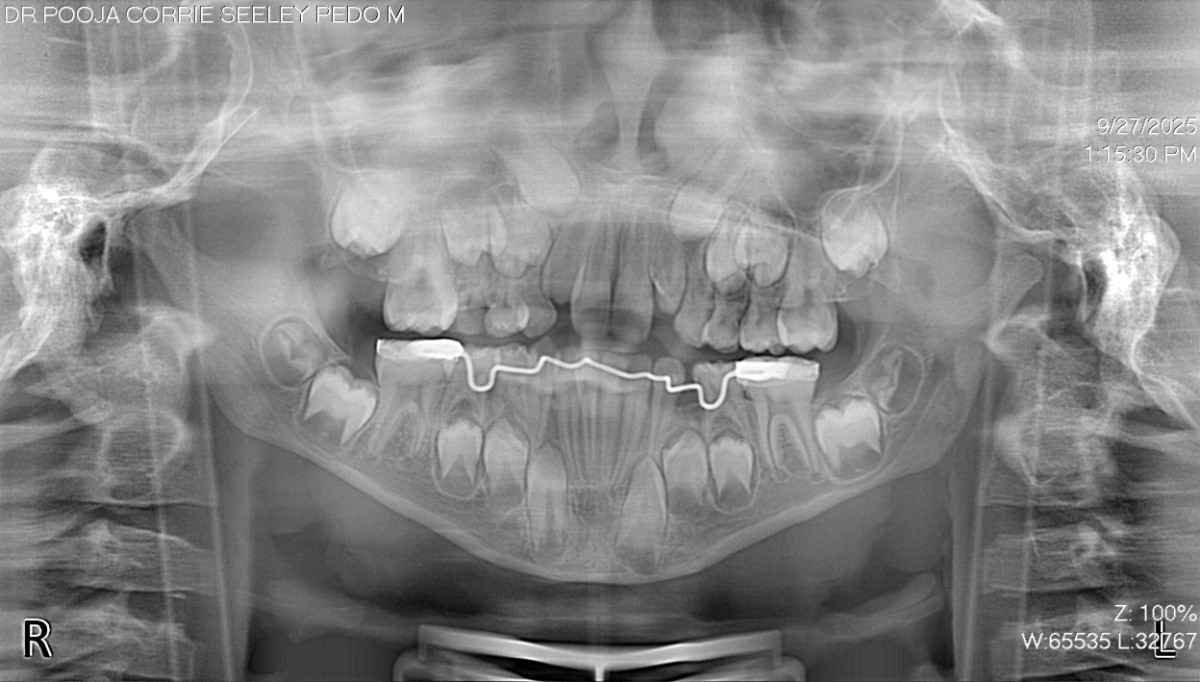

The diagnosis was accurate due to clinical and radiographic examination, & the lower primary molar is prematurely exfoliating. The clinical examination reveals that adjacent teeth have begun to fill the gap. An X-ray deprived of visible space and a 5-year loss potential revealed emerging permanent tooth buds in anticipated sites. Dr. Pooja was treated using a designed lingual holding arch with U-loops. The device helps to stabilize the molars to allow the adjustment to various mandible development. The parents were thoroughly informed about the process, benefits, and care needs were clarified.

The local anesthesia and isolation of U-loops through the rubber dam were optimal in providing ideal hygiene around the lower molars of the child, which Dr. Pooja cemented using a custom lingual holding arch.

Magnification tools were used to guarantee precise positioning. The U-loops were built into the arch to increase in size as the child develops. The whole process was effective and aimed at reducing the chair-time as much as possible and maximizing the comfort as much as possible.